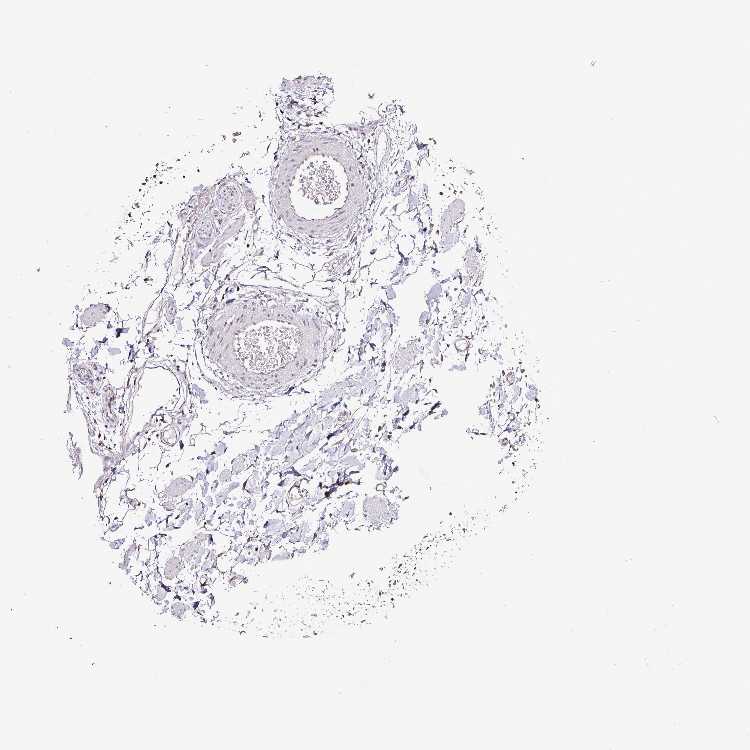

ADIPOSE TISSUE - Antibody stainingi

Antibody staining in the annotated cell types in the current human tissue is reported as not detected, low, medium, or high, based on conventional immunohistochemistry profiling in selected tissues. This score is based on the combination of the staining intensity and fraction of stained cells.

Each image is clickable and will lead to virtual microscopy that enables deeper exploration of all samples and also displays staining intensity scores, fraction scores and subcellular localization as well as patient and tissue information for each sample.

Antibody HPA041120

Adipocytes Medium